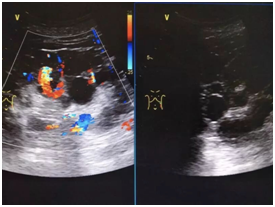

B超检查是超声波检查的一种,是一种非手术的诊断性检查,通过B超可获得人体内脏各器官的各种切面图形比较清晰。B超比较适用于肝、胆肾、膀胱、子宫、卵巢等多种脏器疾病的诊断。 ···...